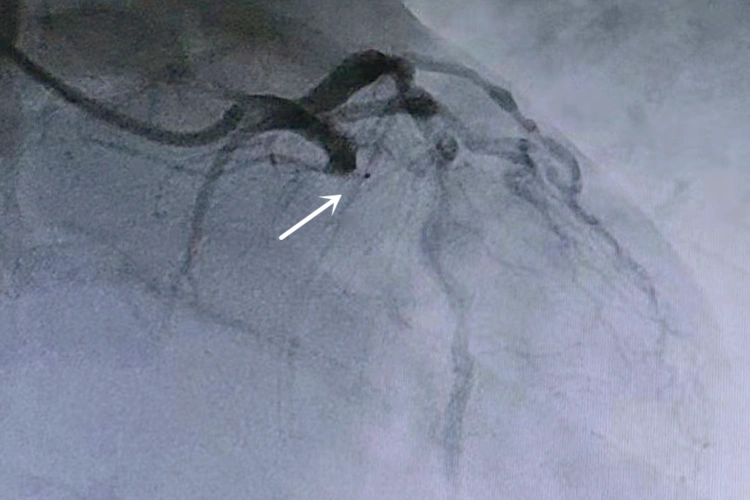

造影显示患者的冠状动脉回旋支近段完全闭塞.(翻拍照片)